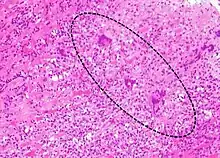

A microscope image of myocarditis at autopsy in a person with acute onset of heart failure | |

The gold standard is the biopsy of the myocardium, in general done in the setting of angiography. A small tissue sample of the endocardium and myocardium is taken and investigated. The cause of the myocarditis can be only identified by a biopsy. Endomyocardial biopsy samples are assessed for histopathology (how the tissue looks like under the microscope): myocardial interstitium may show abundant edema and inflammatory infiltrate, rich in lymphocytes and macrophages. Focal destruction of myocytes explains the myocardial pump failure.[10] In addition samples may be assessed with immunohistochemistry to determine which types of immune cells are involved in the reaction and how they are distributed. Furthermore, PCR and/or RT-PCR may be performed to identify particular viruses. Finally, further diagnostic methods like microRNA assays and gene-expression profile may be performed.